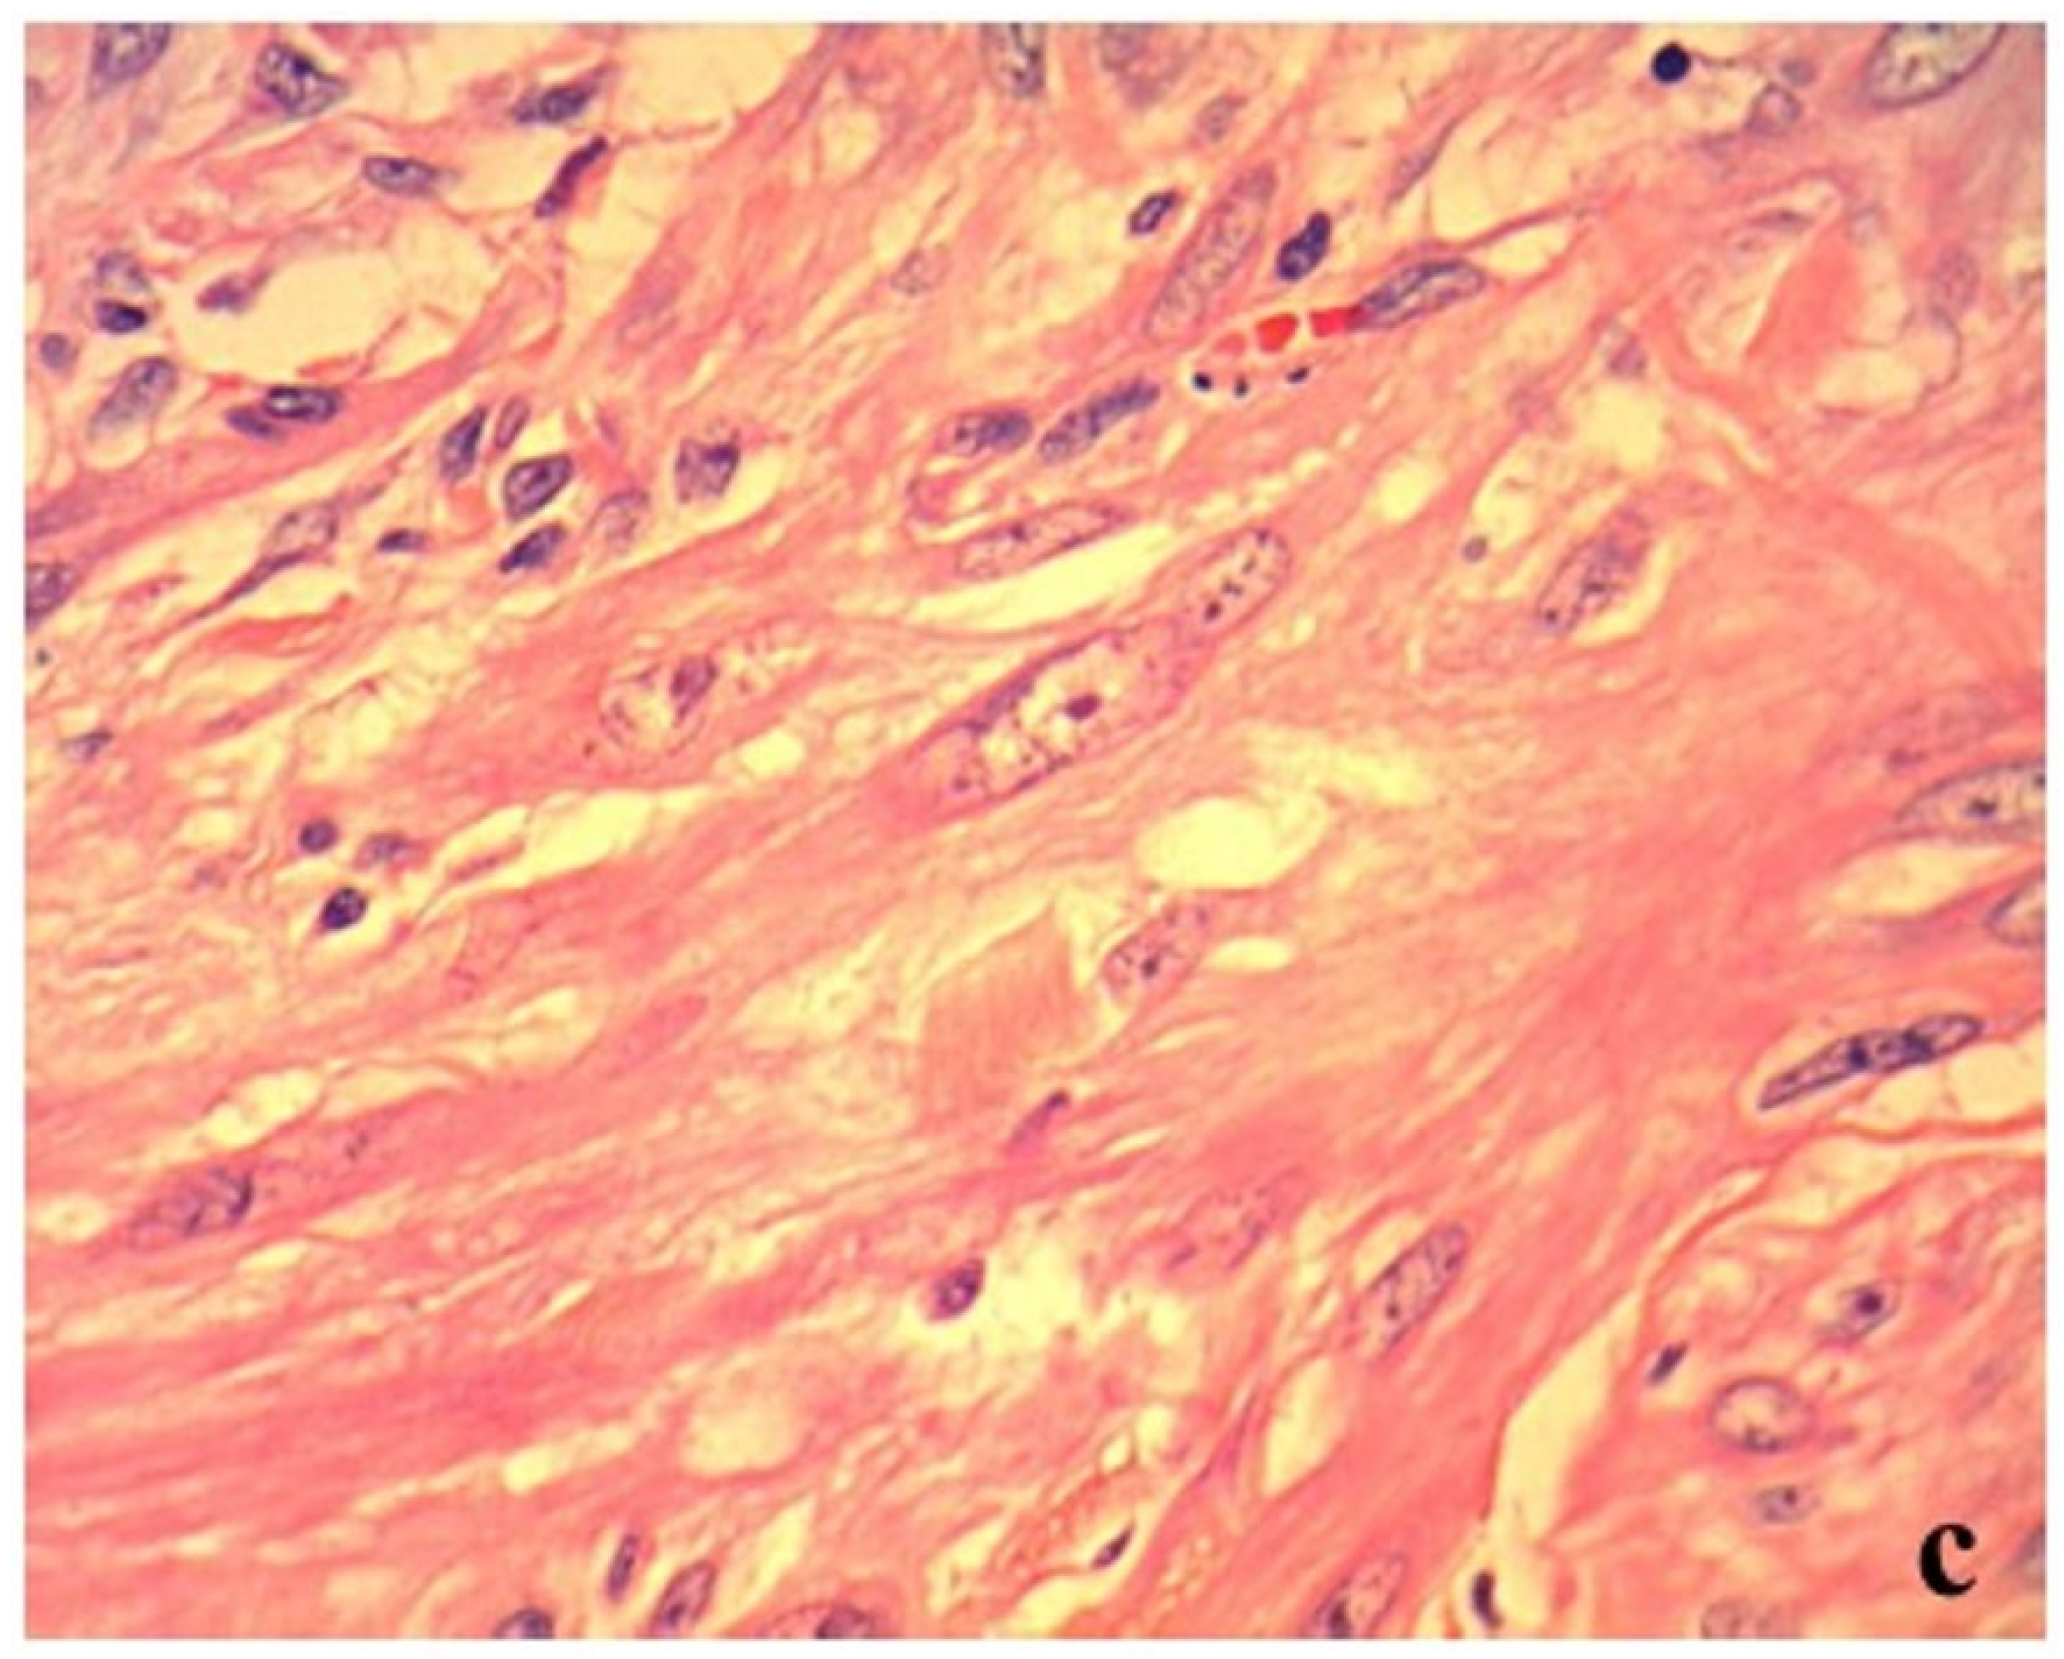

On day 2, an additional blood test performed before surgery revealed normal levels of total bile acid (5.0 μmol/L; RI, 0–15.3) (IMMUNO AU10V; FUJIFILM Corporation, Tokyo, Japan), prothrombin time (8.1 s; RI, 7.4–8.4), activated partial thromboplastin time (17.1 s; RI, 12.0–24.0), fibrinogen concentration (185 mg/dL; RI, 150–350) (COAG2; Wako, Osaka, Japan), and increased D-dimer concentration (53.9 μg/mL; RI, <2.0) (SpeLIA; Precision System Science, Chiba, Japan). All examinations were performed in our veterinary hospital. Anesthesia for laparotomy was introduced using propofol (Propoflo; Zoetis, Tokyo, Japan) and was maintained using isoflurane (Isoflurane for animal, Intervet, Tokyo, Japan). Atropine (Atropine sulfate injection; VEDECO, Missouri, USA), midazolam (Dormicum; Astellas, Tokyo, Japan), and butorphanol (Vetorphale; Meiji, Tokyo, Japan) were administered as pre-medications. Physiological saline (Otsuka normal saline; Otsuka, Tokyo, Japan) supplemented with 5% glucose (Otsuka glucose injection; Otuka, Tokyo, Japan) was administered as a fluid during laparotomy. The intraperitoneal mass (9 × 7 × 5 cm) originated from the jejunum, protruding from the serosal surface (Figure 2a). Hemoperitoneum and bleeding from the mass were not observed (Figure 2a). There were no findings of metastasis to other organs and the macroscopic appearance of the liver was normal. The portion of the jejunum harboring the mass was resected, and end-to-end anastomosis was performed. Full-thickness biopsy of the proximal jejunum and liver were performed simultaneously. Joint aspiration was performed to rule out systemic lupus erythematosus (SLE) at the time of surgery and revealed normal fluid levels. Postoperatively, intravenous infusions of acetic acid Ringer’s fluids (Soldem 1; Termo, Tokyo, Japan), meloxicam (0.2 mg/kg (0.09 mg/lb), subcutaneous injection (SC) (Metacam; Boehringer Ingelheim, Tokyo, Japan) for pain relief, cefalexin (20 mg/kg (9.1 mg/lb), SC, q 12 h) (Cefalexin; Nichi-iko, Toyama, Japan) for prevention of postoperative infection, and dalteparin Na (Fragmin 100 U/kg (45.4 U/lb), SC, q 12 h) (Nichi-iko, Toyama, Japan) for prevention of thrombus were administered.

The histopathological examination of the surgically resected mass revealed a mild atypical monomorphic proliferation of non-epithelial cells, exhibiting a spindle shape with abundant eosinophilic cytoplasm and resembling smooth muscle. Tumor cells were classified as malignant based on anisonucleosis, the increased nuclear–cytoplasmic ratio, and the presence of prominent nucleoli (Figure 2c). These findings indicated leiomyosarcoma. The mass had developed in the extraluminal space of the intestinal tract (Figure 2b). However, there was no transmural invasion of the tumor in the mucosa. Moreover, no intestinal bleeding was detected, but the lymphatic vessels on the mucosal surface were dilated (Figure 2b). In the jejunum proximal to the tumor, lymphangiectasia without any inflammatory changes was observed. In the liver, multifocal necrotic foci with infiltration of neutrophils and macrophages and bleeding were observed. We could not confirm whether these histopathological findings were caused by transient hypoxia due to anemia or whether they existed previously. All pathological examinations and subsequent diagnoses were confirmed by board-certified veterinary pathologists at commercial laboratories.

Figure 2. Macroscopic and histopathological findings of the surgically resected mass. (a) Macroscopic findings: The mass protruded from the serosal surface of the jejunum. (b) Histopathological findings (low-power field): The mass was located in the extraluminal space of the intestinal tract, but there was no transmural invasion of the tumor in the mucosa. No intestinal bleeding was detected, and lymphatic vessels on the mucosal surface were expanded. (c) Histopathological findings (high-power field): The mass revealed a mild atypical monomorphic proliferation of non-epithelial cells, exhibiting a spindle shape with abundant eosinophilic cytoplasm and resembling a smooth muscle. Tumor cells were classified as malignant based on anisonucleosis, the increased nuclear–cytoplasmic ratio, and the presence of prominent nucleoli.